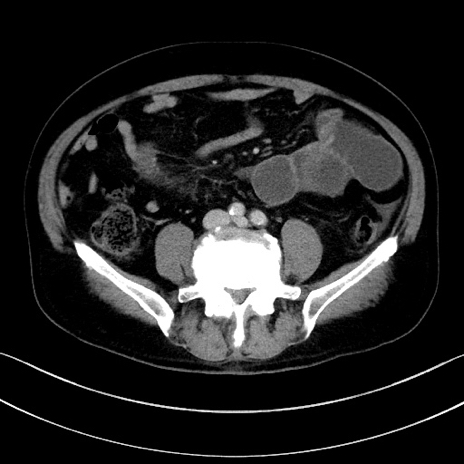

症例15(横断像)

【症例】70歳代男性

【主訴】腹痛

【現病歴】今朝から腹痛あり。全体的に痛い。特に左上の方。排ガスが今日はない。冷や汗が出る。

【既往歴】直腸癌術後

【身体所見】左側腹部〜上腹部に圧痛あり。腹膜刺激症状明らかなではない。軽度反跳痛。左下腹部に術後瘢痕あり。

【データ】WBC 7700、CRP 0.02